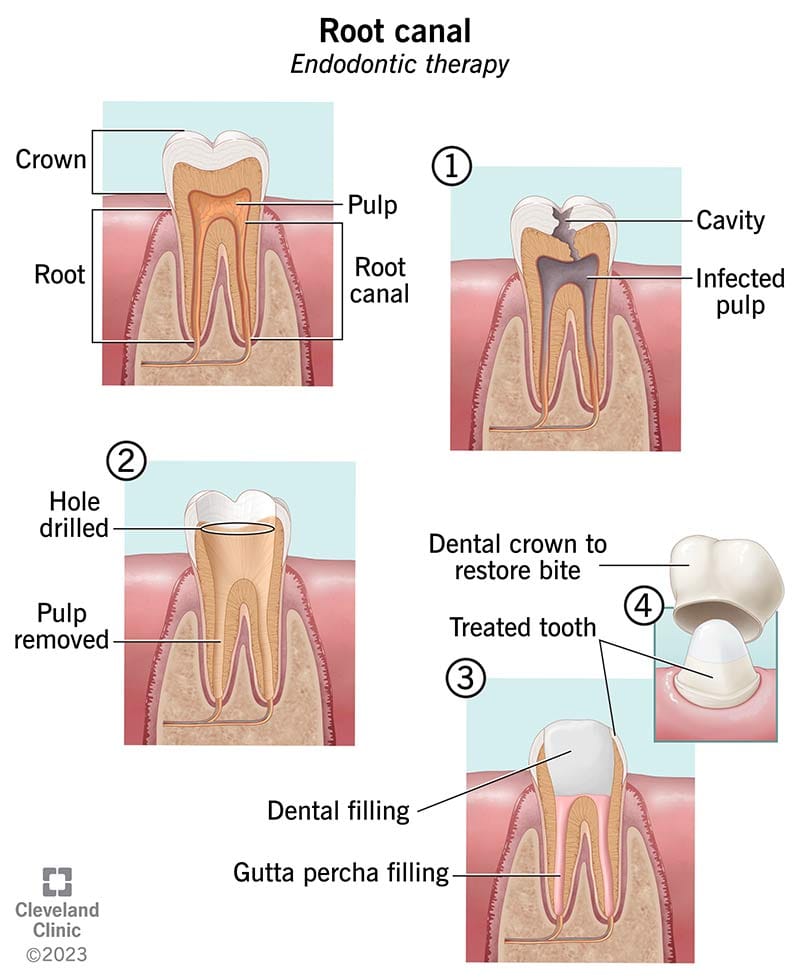

Root canal treatment is a common dental procedure that helps save an infected or damaged tooth. However, many people have questions and concerns about this treatment. In this blog post, we will provide answers to some of the most frequently asked questions about root canal treatment. By addressing these concerns, we aim to alleviate any fears or misconceptions you may have, helping you make informed decisions about your dental health.

What is a root canal treatment?

A root canal treatment, also known as endodontic therapy, is a dental procedure performed to save a tooth that has an infected or inflamed dental pulp. The dental pulp, which consists of nerves, blood vessels, and connective tissue, is located inside the tooth's root canals.

Why might I need a root canal?

How is a root canal procedure performed?

The root canal procedure typically involves the following steps: